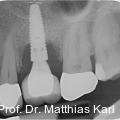

Parallel zur Entwicklung verkürzter Behandlungskonzepte haben sich auch die Außengeometrien zahnärztlicher Implantate hin zu aggressiveren Gewindeformen und konischen Grundkörpern entwickelt. Fotos: © Prof. Dr. Matthias Karl